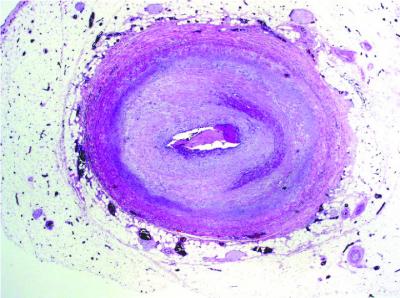

Heart-transplant Blood Vessel

image: This is a close-up of a heart-transplant blood vessel in chronic rejection. view more

Credit: UCLA Immunogenetics Center

The team focused on the mechanism behind narrowing of the donor's grafted blood vessels, which blocks blood from reaching the transplanted organ. Starved of oxygen and other nutrients, the organ eventually fails, forcing the patient back on the transplant waiting list.